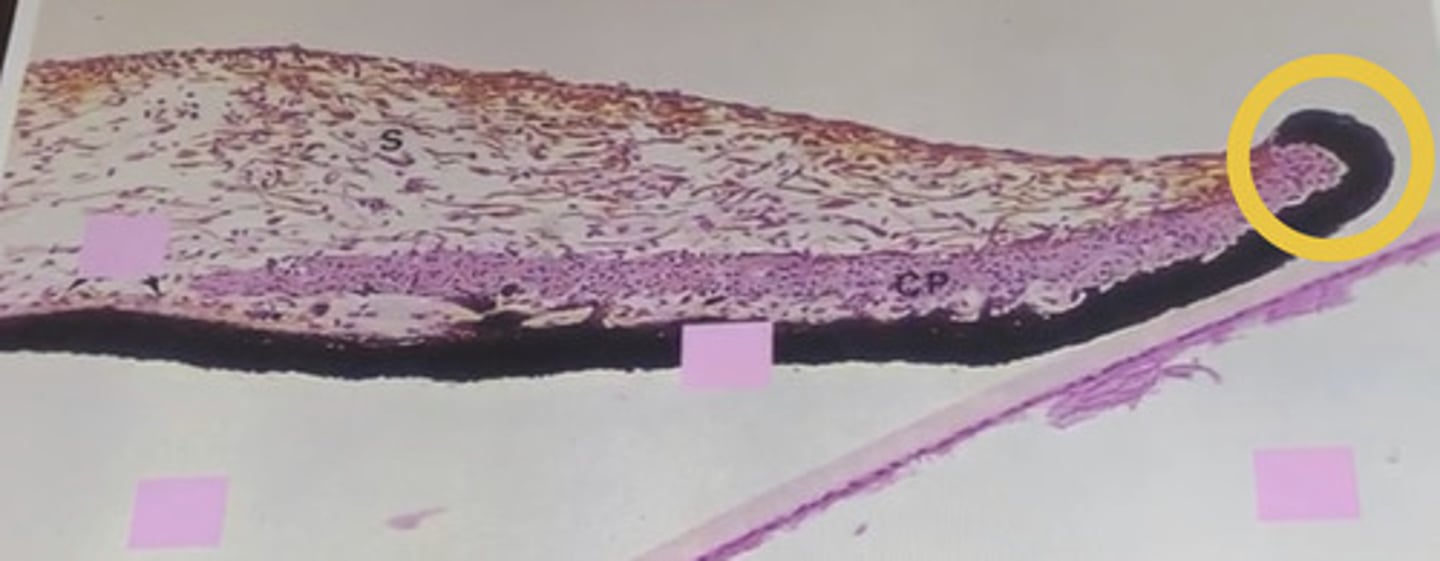

What are the five layers of the iris?

1) anterior border layer

2) stroma

3) muscular layer: sphincter, dilator

4) anterior iris epithelium

5) posterior iris epithelium

What types of cells does the anterior border layer of the iris contain? How are they organized?

melanocytes and fibroblasts; fibroblasts concentrate on the surface overlying melanocytes beneath

What is the function of the anterior border layer?

first pigmented cells to block light, helping the iris to serve as effective aperture stop, and to determine eye color

What is the iris stroma composed of?

spongy mixture of melanocytes, fibroblasts, collagen, and blood vessels

Which epithelial layer has heavy pigmentation?

posterior epithelial layer

Which epithelial layer forms the dilator muscle?

anterior epithelial layer -> it is the myoepithelium from which the dilator muscle arises